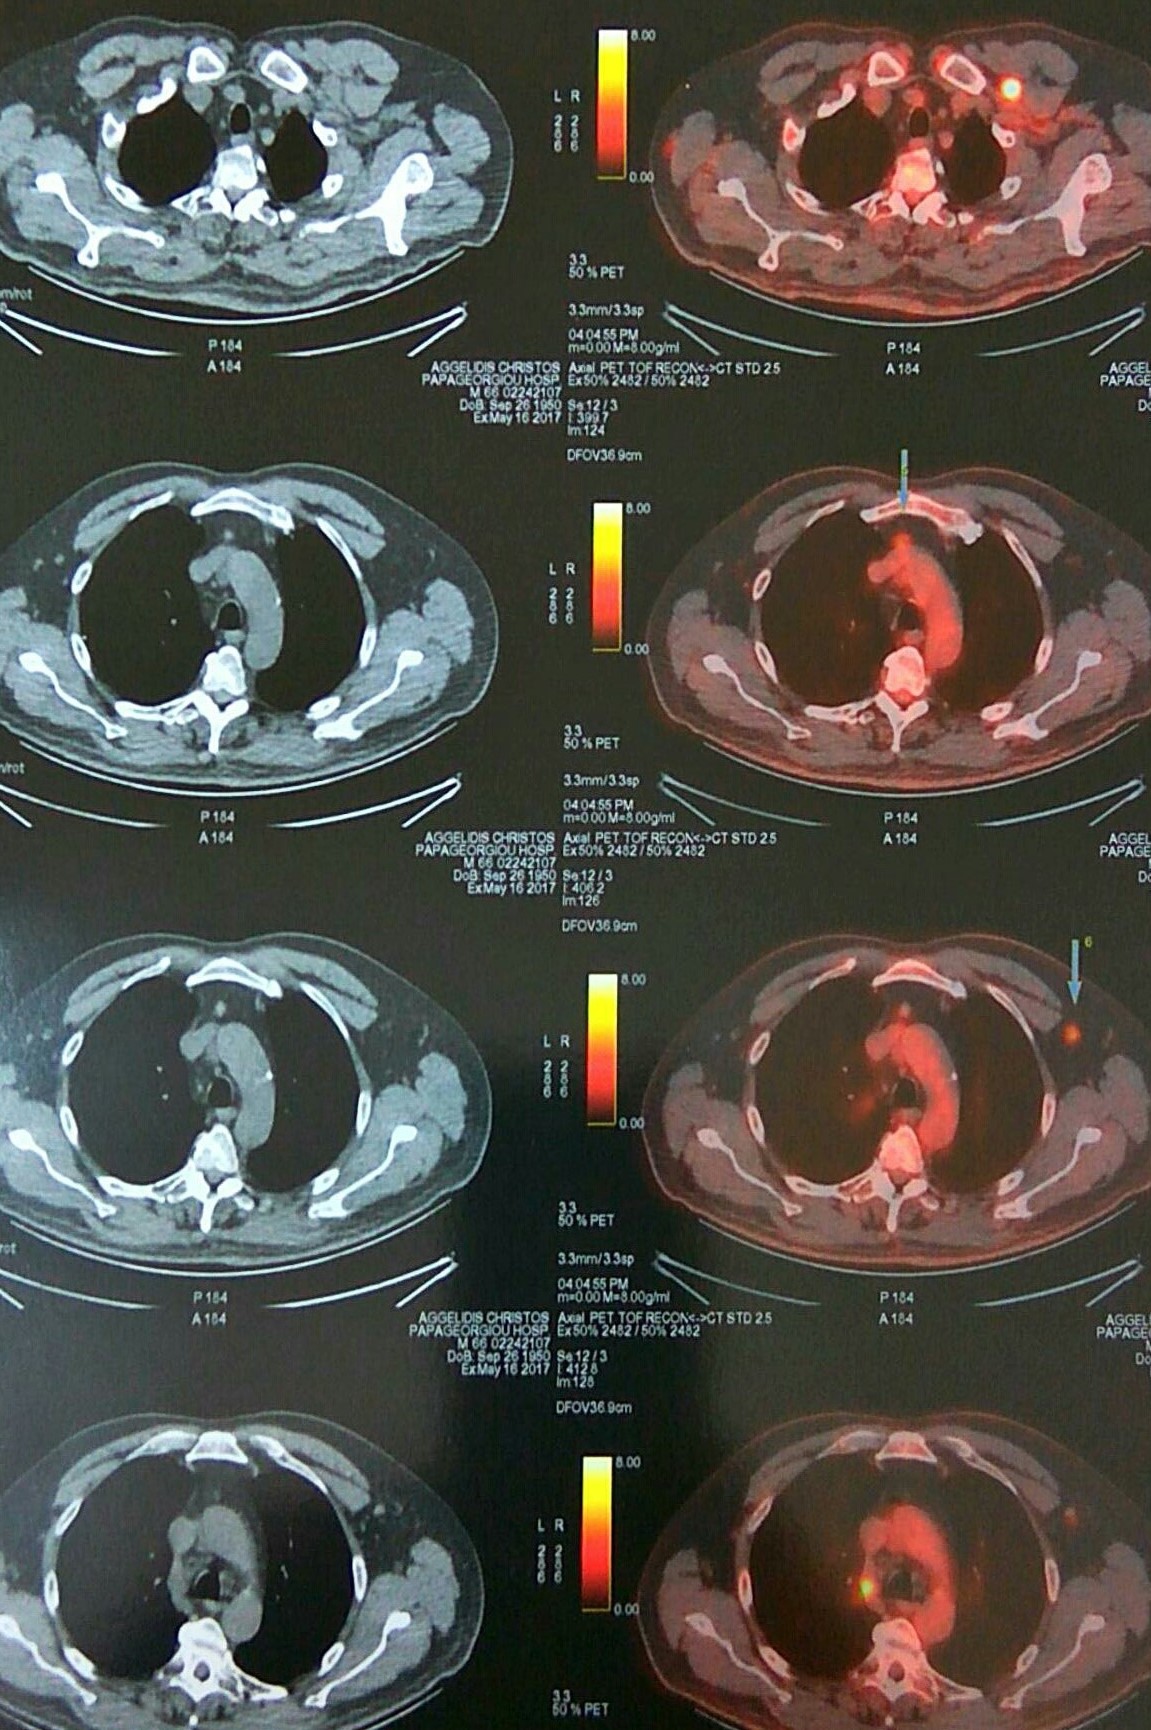

Αμφοτερόπλευροι πνευμονικοί όζοι ενδεικτικοί μεταστάσεων μελανώματος (Ευγενική παραχώρηση Dr. V. Penopoulos)